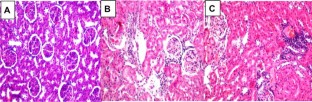

We investigated the action of caffeic acid in regulating miR-636 expression level in kidney of streptozotocin-induced diabetic rats. Streptozotocin-induced diabetic rats were orally treated with caffeic acid at 40 mg/kg/day for 8 weeks. At the end of the treatment, body and kidney weight and blood glucose levels were determined, blood, urine, and kidneys were collected for biochemical and histological examination. Expression levels of miR-636 were determined in liver by qRT-PCR. Induction of diabetic nephropathy by streptozotocin was evidenced by displayed elevated levels of serum creatinine, blood urea nitrogen, microalbuminuria and urinary albumin/creatinine ratio in addition to renal hypotrophy. Caffeic acid (CA) can ameliorate renal damage and significantly decreased the fasting blood glucose, cholesterol and triglyceride in diabetic rats. CA treatment improved histological architecture in the diabetic kidney. CA significantly down regulate miR-636 expression level in the kidney of diabetic rats in comparison to healthy group. Overall, caffeic acid down regulates miR-636 expression level which is involved in development of diabetic nephropathy and might therefore be potential attractive therapeutic agent to pursue in DN.

Fig. 2